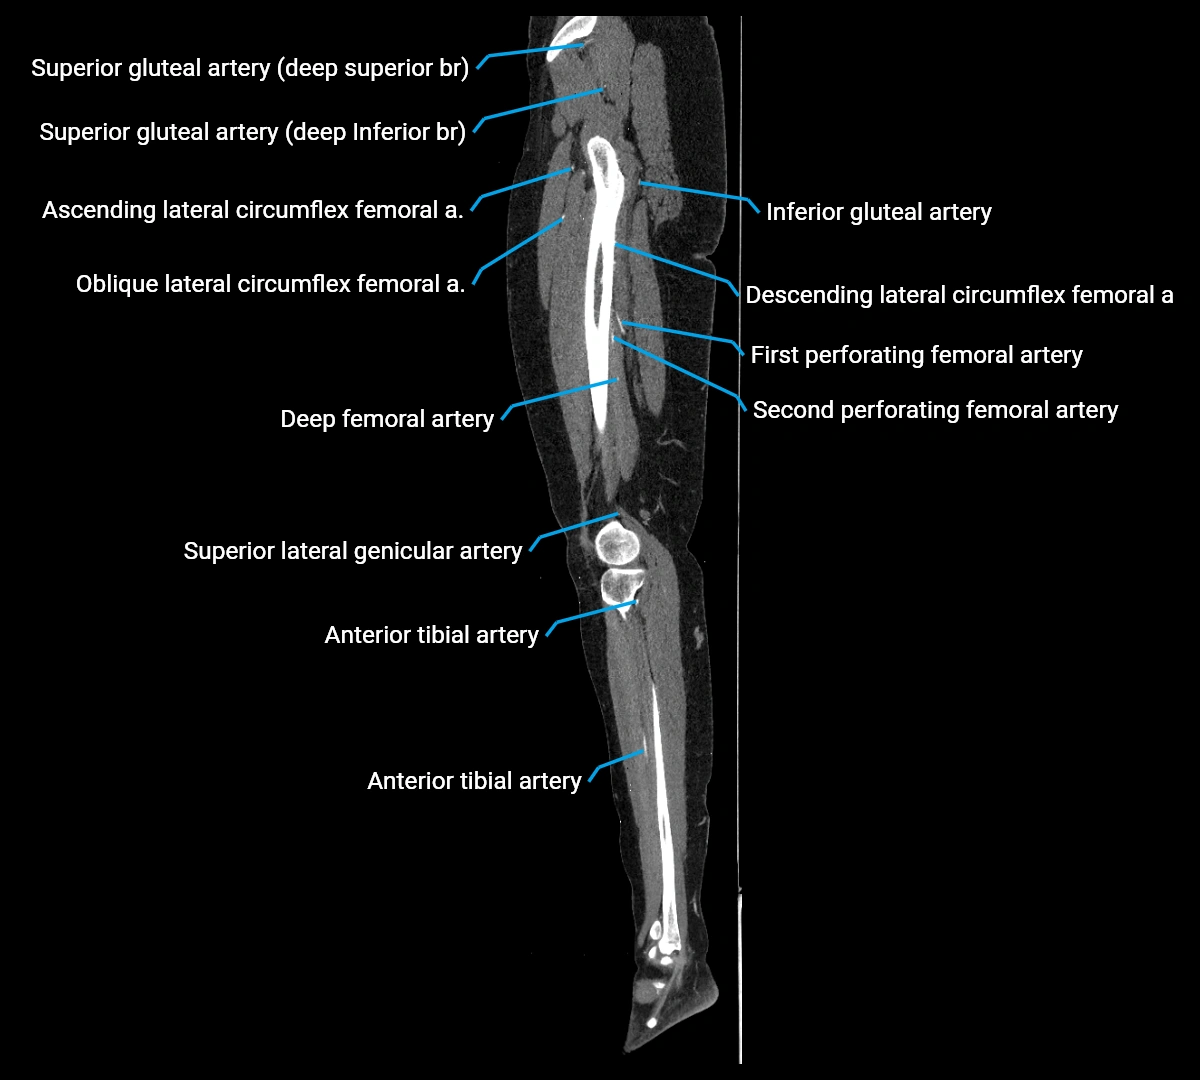

CT images

image